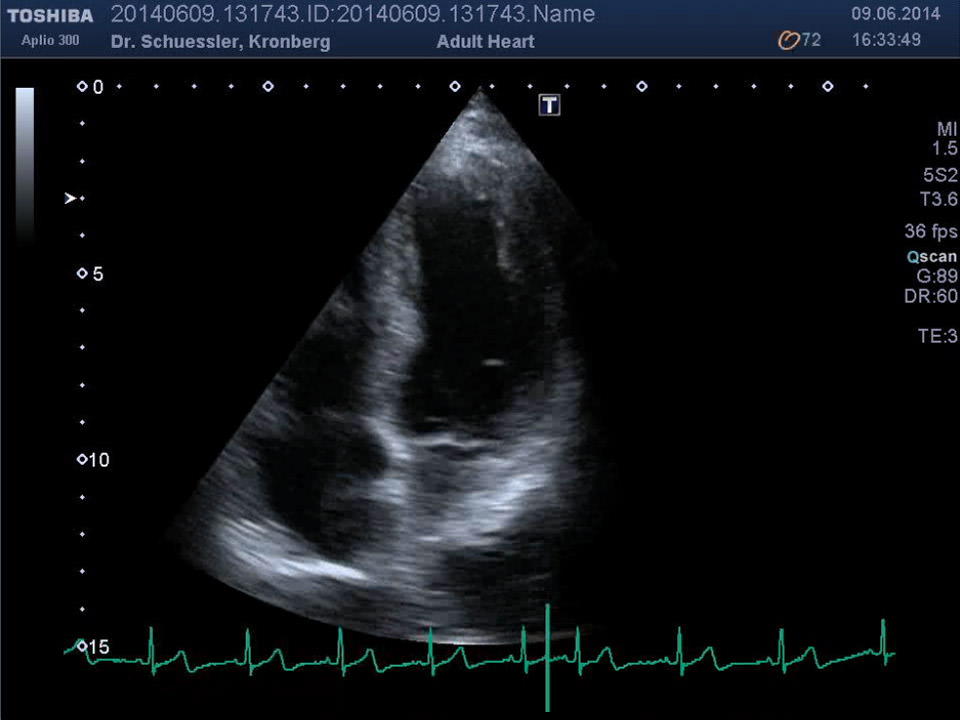

Die Ultraschalluntersuchung des Herzens erlaubt, auf einem nicht belastenden Weg, eine umfangreiche Darstellung des Herzens. Unter Hinzunahme der Farbdopplertechnik kann eine ausführliche Beurteilung der Strukturen und der Funktion des Herzens erfolgen.

Moderne Auswertungsalgorithmen wie das „Wall Motion Tracking“ erlauben eine isolierte, hochauflösende Darstellung und Analyse der Bewegung und Funktion einzelner Segmente des Herzmuskels.